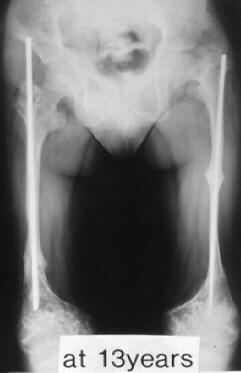

A 18-years-old boy. Body height 114cm. Sillence type III.

The first visit was at 4 years of age. He sustained 16 fractures in L/E and 30 fractures in U/E. He underwent 9 operations. He had 80 degrees progressive scoliosis and recently underwent posterior spinal fusion with internal instrumentation. He obtained his initial gate at 18 months of age, and had been practical ambulator until 9 years old. However, the diameter of the femur which was 15mm at 7 years of age had started to decrease prior to the functional aggravation. He eventually became a non-ambulator after the ankle joint fracture at 9 years old. The diameter of the right and left femur at the age of 18 were 7 and 8 mm respectively.